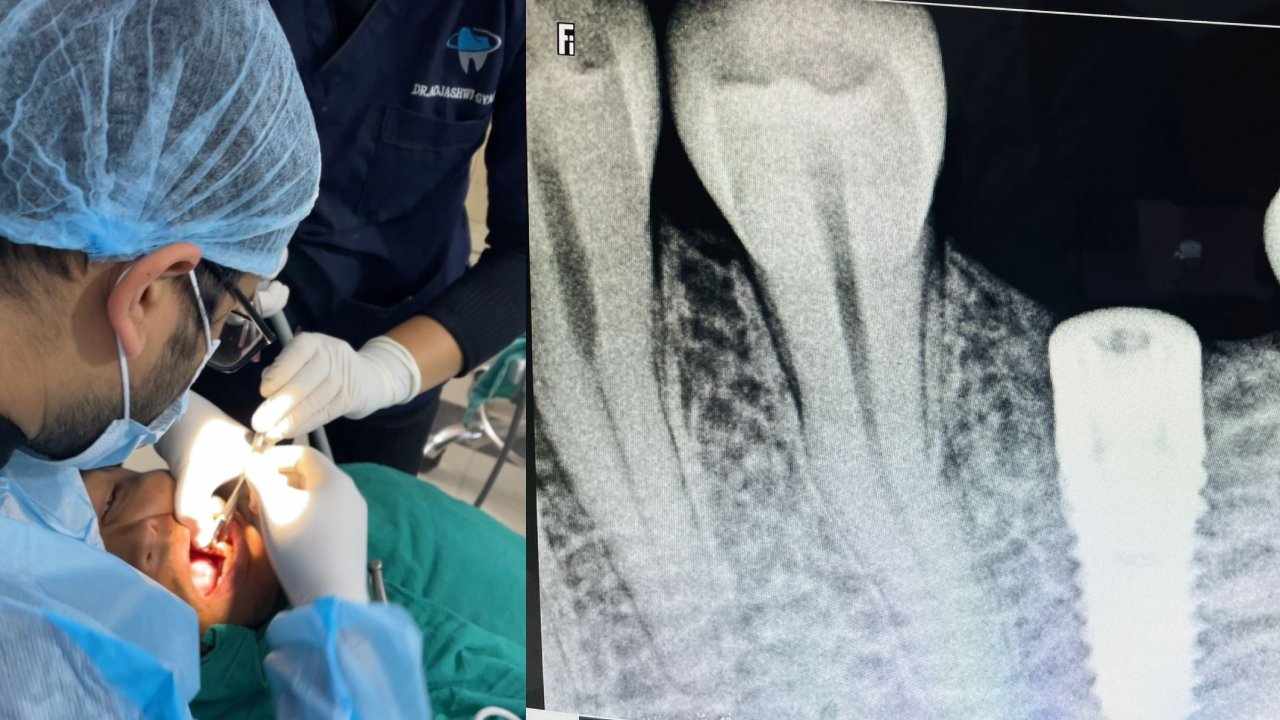

बुटवल । लुम्बिनी प्रादेशिक अस्पतालमा पहिलो पटक दाँतको प्रत्यारोपण गरिएको छ । अस्पतालकी दन्त चिकित्सा प्रमुख कन्सल्टेन्ट डेन्टल सर्जन वर्षा थापाका अनुसार मंगलबार दातको सफल प्रत्यारोपण (डेन्टल इम्प्लान्ट) गरिएको हो ।

विशेषज्ञ सेवालाई बिस्तार गर्दै गईरहेको लुम्बिनी प्रादेशिक अस्पतालमा पछिल्लो समय दाँत तथा मुख रोगका सफल उपचारहरु हुँदै आएको थापाले बताइन् । सीमित स्रोत र साधनका बाबजुद पनि अस्पतालमा गुणस्तरीय र अति कम शुल्कमा दाँतका विभिन्न खाले उपचार उपलब्ध हुने उनले बताइन् ।

मंगलबार पहिलो पटक दाँतको सफल शल्यक्रियासँगै सेवाग्राहीहरु अब निजी स्वास्थ्य संस्थामा धाउनु पर्ने बाध्यता अन्त्य भएको डा. थापाले उल्लेख गरिन् । शल्यक्रिया डा. थापाको नेतृत्वमा डा. सम्राट पहाडी, डा. सुचना अधिकारी, डा. नारायण पोखरेल र डा. रिचा भडेलको टोलीले गरेको थियो ।